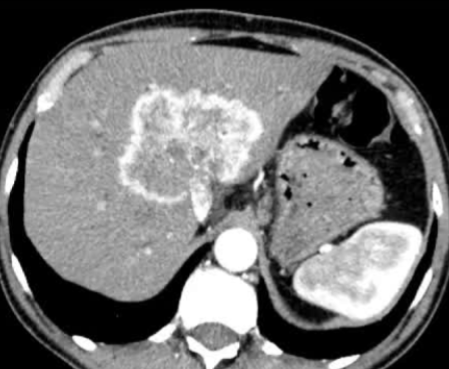

· 单中心、样本量小; 83 岁的女性,体重超标 40 毫米单发 ICC(S7-S8) 中肝静脉和右肝静脉浸润性,活检:非酒精性脂肪性肝炎(慢性肝病),马斯氏(MaS)病(30%)

考虑采用“三步策略 TARE→ PVE → Surgery”方案 剂量活性:1.56 和 3.16 GBq